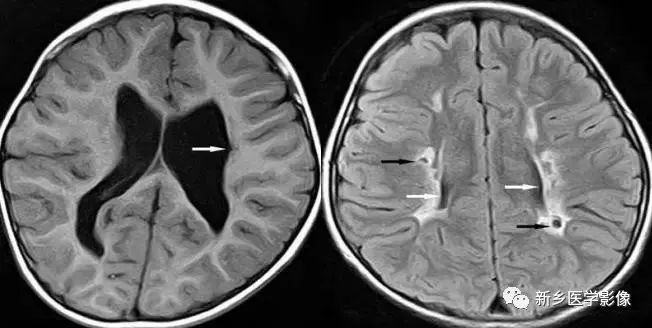

❺ 脑室周围白质软化症

主要与缺血缺氧及感染有关。常见于早产儿,是造成早产儿脑瘫的主要原因。

由于脑室周围白质的血供分别来自脑室区和远脑室区的终动脉,未成熟儿终动脉深穿支的侧支循环尚未建立,而胚胎晚期脑室周围白质对缺血缺氧敏感,所以,脑室周围自质软化症多见于早产儿。

由于病灶常为双侧性,故双侧侧脑室多同时扩大。脑白质内软化灶在CT扫描时表现为白质内斑片状低密度灶,MR上T1加权图呈低信号,T2加权图呈高信号。

❻ 脑室周围白质软化症

主要与缺血缺氧及感染有关。

常见于早产儿。原因与胚胎期脑部损害发生的时间有关:胚胎早中期脑损害主要引发发育畸形,晚期主要引起脑血管改变。

由于侧脑室周围有软化萎缩,故扩大的侧脑室外缘常不规则、不光整,这种不规则、不光整是本病引起脑室扩大的特。另外,本病均表现有脑白质量减少及脑白质内斑片状软化病灶,脑白质减少严重时表现为部分区域白质消失,脑皮层与脑室侧缘接近甚至相连。CT表现为斑片状低密度灶。MR T1WI上呈低信号,T2WI呈高信号。